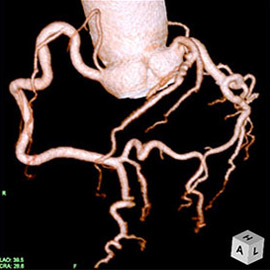

80列マルチスライスCTで撮影した画像

心臓(冠動脈)

主に狭心症や心筋梗塞などの診断